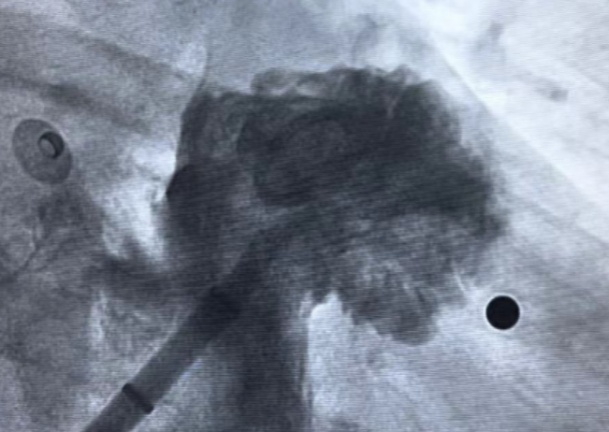

龚辉主任团队慎重考虑,在与患者及家属充分沟通的情况下,决定为患者进行射频消融联合左心耳封堵一站式手术。经过心内科团队近3小时的不懈努力,患者的手术过程十分顺利,有效预防了患者因房颤导致的心源性脑卒中再次发生的可能,也减少了房颤可能导致的心力衰竭。

对于某些不能接受或不宜长时间使用抗凝治疗的房颤患者,医生可能会推荐进行左心耳封堵手术。这是一种微创手术,医生会通过血管将一个特制的封堵器送到左心耳,并在那里展开手术,从而隔离左心耳,防止血栓形成并进入血流。